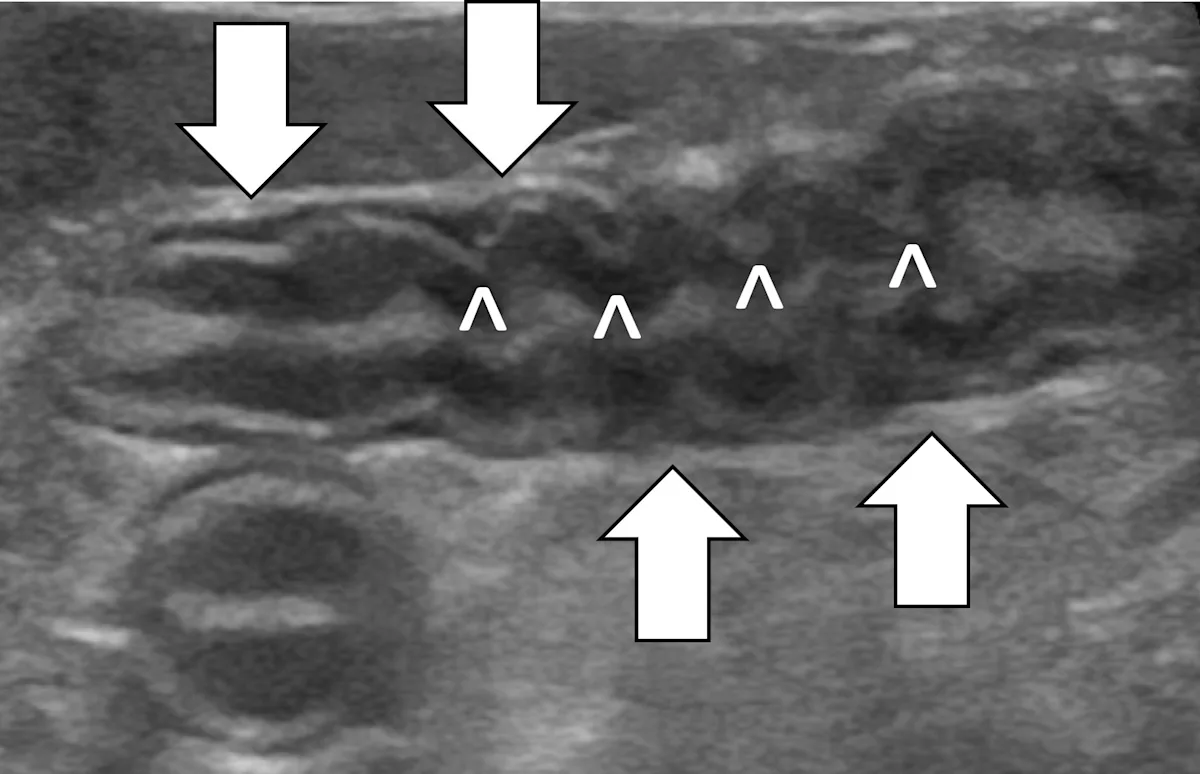

Linear foreign body obstructions occur when an object (eg, string, cloth) becomes stuck orally but extends aborally through the intestinal tract. Peristaltic contractions typically cause the small intestine to travel orally, eventually bunching. As a result, ultrasonographic findings include intestinal bunching (ie, plication) with or without a hyperechoic linear structure coursing through the lumen of the affected bowel (Figure 4).9-12 In some cases, trapped gas can cause a line that can be mistaken for the linear foreign body. Plication should not be confused with normal peristalsis or corrugation (Figure 5). With corrugation, the serosal margin is normal, and the mucosa and submucosa are undulant; with plication, the serosal margin is affected.14 In chronic cases, the mesentery surrounding the affected bowel may become hyperechoic, which can help identify the site of obstruction. Sterile inflammation and transudation may then result in focal accumulation of a small volume of free fluid. Mesenteric changes and peritoneal effusion also increase concern for bowel rupture and septic peritonitis. Patients may have concurrent findings of pyloric outflow or small intestinal mechanical obstruction, depending on the size and nature of the ingested cloth or string.

Abdominal ultrasound of an 11-month-old neutered male domestic shorthair cat with a surgically confirmed toy ball connected to a linear foreign body anchored in the pylorus (asterisk). The proximal duodenum is plicated (black arrows) with a hyperechoic linear structure (white arrows) coursing through the center. Normal small intestine can be seen adjacent to the plicated duodenum (caret).

Abdominal ultrasound of an 8-year-old spayed miniature pincher with inflammatory bowel disease and pancreatitis. The mucosal and submucosal layers of a loop of jejunum are undulating (carets), but the serosal margin remains smooth (arrows).